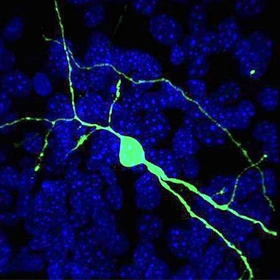

A human neuron (green) integrates into a brain circuit from a mouse with Huntingtons disease.